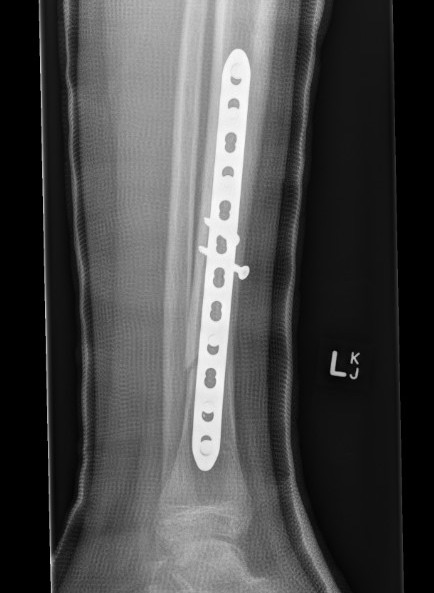

Fixation

- Grade I - reduced +/- percutaneous pinning, long leg cast once wound closed

- Grade II & III - external fixation